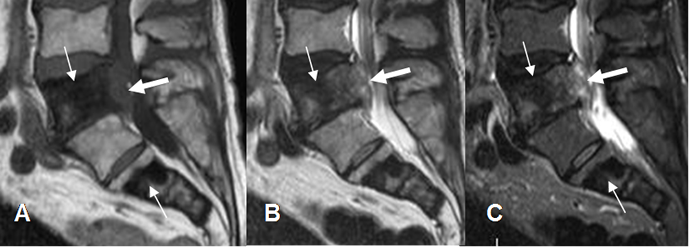

Fig 229. Tumor metastásico.

A: RM sagital en T1. Lesiones hipointensas en D12 y L1, por enfermedad metastásica de próstata.

B: RM sagital en T1 con contraste. Realce con halo hiperintenso, signo de enfermedad metastásica.